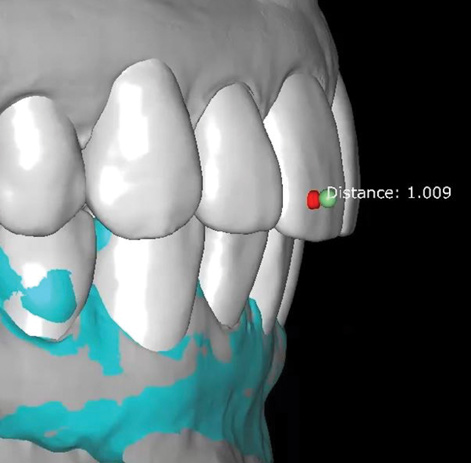

Fig 8. Scans used to mock-up desired restorative result using modeling software. The teal-green areas represent the current tooth form, and the white areas show the desired or digital wax-up. A reduction of 1.009 mm was required prior to preparation, making endodontic treatment likely if orthodontic treatment is not considered.

Figure 8

Fig 9. Scans used to mock-up desired restorative result using modeling software. The teal-green areas represent the current tooth form, and the white areas show the desired or digital wax-up. A reduction of 1.009 mm was required prior to preparation, making endodontic treatment likely if orthodontic treatment is not considered.

Figure 9